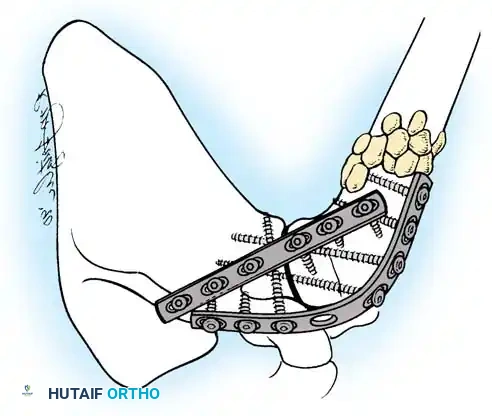

The most robust biomechanical construct involves a heavy, malleable plate (such as a 10- to 14-hole 4.5mm pelvic reconstruction plate or a dynamic compression plate). The plate is meticulously contoured to lie flat along the spine of the scapula, bend over the acromion, and extend down the lateral shaft of the humerus.

Screws are placed sequentially:

1. Scapular Spine: Cortical screws are placed into the dense bone of the scapular spine.

2. Acromiohumeral Fixation: Screws are passed through the plate, across the acromion, and into the humeral head.

3. Glenohumeral Fixation: Long, fully threaded cortical or cancellous screws are directed through the plate, through the humeral head, and deep into the glenoid neck and vault. This is the most critical step for achieving compression across the primary fusion site.

4. Humeral Shaft: The distal portion of the plate is secured to the humeral diaphysis.

If additional stability is required, or if bone quality is poor, a second plate (double plating technique) can be applied posteriorly.

Radiographic confirmation of a contoured reconstruction plate achieving rigid acromiohumeral and glenohumeral compression.